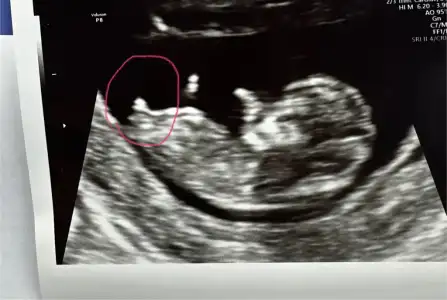

Arkasi dönük bilmem ki tahmin olur mu 11+4 teki görüntü buydu. (Şimdiye kadarki tek görüntü)

Devlet Hastanesi'nde bana doktor hiç görüntü vermiyor 12+4 görüntüsü yok. Neden vermiyorlar bilmiyorum. Bu durumu yaşayan arkadaşlar var mı. İsteyince mı veriyorlar acaba

İlk birkaç defa ben de devlete gitmiştim, bana da vermemişlerdi. Hatta ben ekrandan kendim fotoğrafını çekmiştim